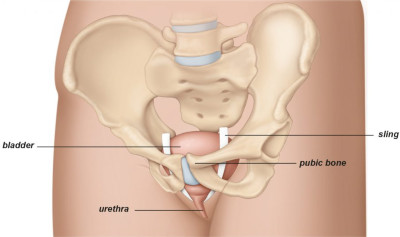

Είναι το συχνότερο είδος ακράτειας στις γυναίκες και οφείλεται στην χαλάρωση του πυελικού εδάφους (Εικ.1) αλλά και στην εμμηνόπαυση.

Εικ.1: Το γυναικείο Πυελικό Έδαφος